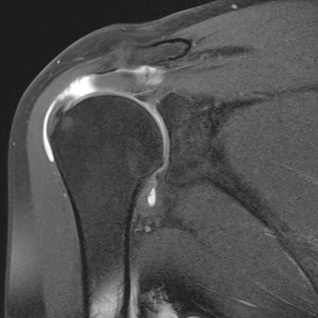

Die Diagnose kann oftmals bereits durch eine gezielte Untersuchung gestellt werden. Zur Beurteilung der Qualität der Sehne, sowie des Ausmasses des Sehnenrisses sind häufig MRI-Untersuchungen notwendig. Gelegentlich genügt eine Ultraschalluntersuchung.

MRI eines Sehnenrisses (weisse Stelle)